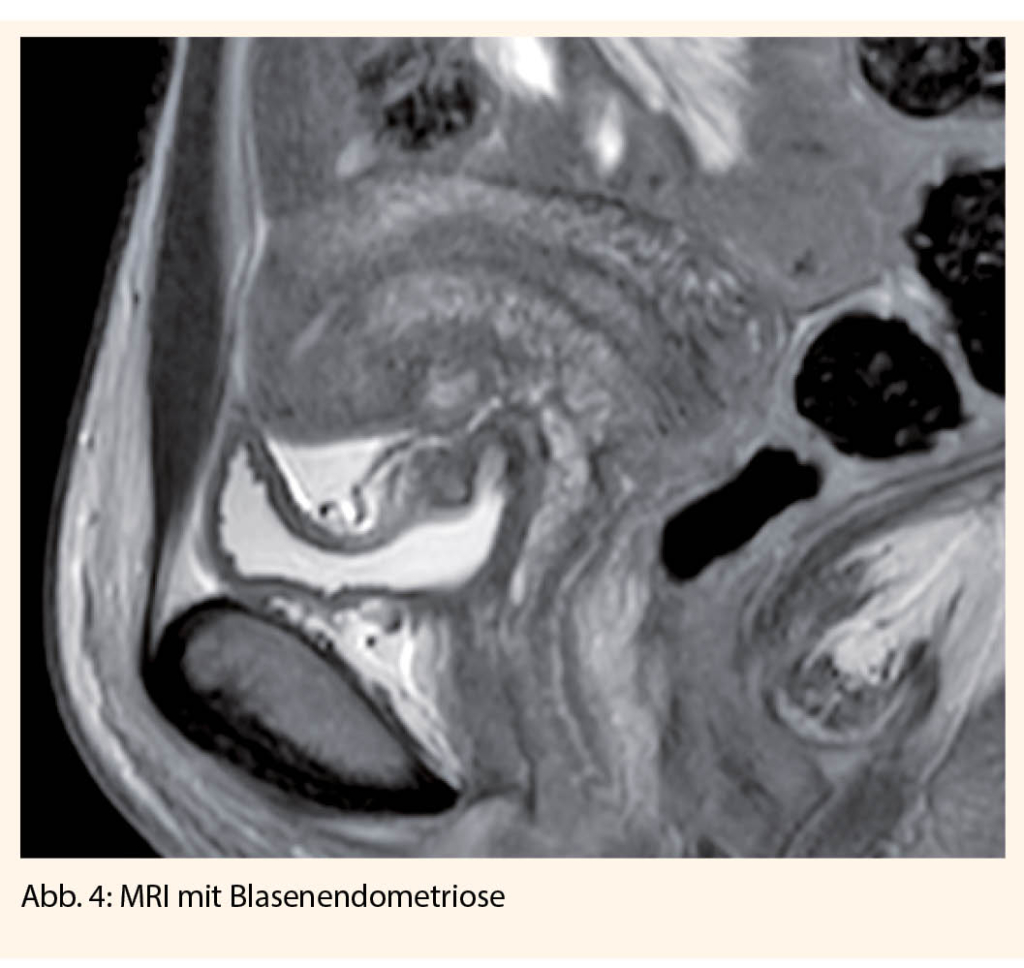

Mittels Ultraschall können durch den erfahrenen Untersucher auch tiefinfiltrierende Herde im Bereich des Septum rektovaginale, der Sakrouterinbänder, der Blase und des Darms dargestellt werden. Bei Hinweisen für eine tiefinfiltrierende Endometriose mit Verdacht auf Darmbeteiligung, Beteiligung der Blase, Ureteren, und auch bei extrapelviner tiefinfiltrierender Endometriose, sollten noch weitere Untersuchungen durchgeführt werden:

• Ultraschall der Nieren zum Ausschluss einer Hydronephrose

• MRT

• Zystoskopie

Bei urologischer Beteiligung der Endometriose (Blase 85%, Ureter 9%) kann ein operativer Eingriff zur Reduktion der Symptomatik und Verbesserung der Schwangerschaftsrate sinnvoll sein. Je nach Infiltrationstiefe muss ein vesikales Shaving oder auch eine Blasenteilresektion durchgeführt werden. Eine alleinige zystoskopische Resektion reicht nicht aus, da die Herde immer transmural gelegen sind. Bezüglich des Ureters können die Eingriffe, je nach Ausdehnung, von einer Ureterolyse, einer Uretersegmentresektion bis hin zu einer Neuimplantation variieren (19).